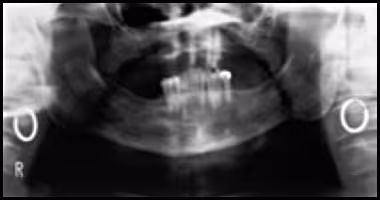

These figures show the effects of positioning the patient’s head too far back: widening of the entire image, loss of the posterior ramus of the mandible (right), accentuated ghosting of the mandible, blurring of the turbinates across the sinus, and pronounced widening of the anterior teeth.

Figure 52A. Panoramic Image.

Figure 52B. Panoramic Schematic.